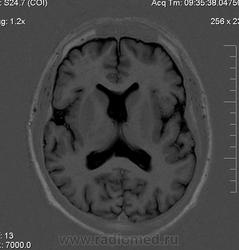

Мужчина 32 лет. Из анамнеза: перинатальное повреждение ЦНС, ДЦП, дизартрия, правосторонний верхний монопарез. С 16 лет приступы эпилепсии.

Аплазия прозрачной перегородки. Шизэнцефалия с открытыми краями в лобно-теменной области слева. Шизэнцефалия с закрытыми краями в лобной области справа? Утолщение коры по контуру расщелин и в области глазничной извилины правой лобной доли. Микрогирия? Гиперостоз костей свода черепа. Уважаемые коллеги, возможно я ошибаюсь, или есть еще аномалия?

Спасибо. Как тогда лучше сформулировать заключение? МР-картина кортикальной дисплазии : двусторнняя шизэнцефалия с утолщением коры по контуру расщелин, микрогирия в лобной области справа, очаг гетеротопии серого вещества в области  глазничной извилины правой лобной доли. Признаки септооптической дисплазии (гипоплазия зрительных нервов, аплазия прозрачной перегородки). Лиссэнцефалии не вижу. Есть сомнения по поводу шизэнцефалии справа (может быть я запуталась в микрогирии и мерещится шизэнцефалия?) Нет ли какой либо анамалии развития черепа?

На мой взгляд, полимикрогирия двусторонняя (конвекситальные отделы дорзальных отделов лобных долей и частично теменных, а также в базальном отделе полюса правой лобной доли) + закрытая шизенцефалия левой лобно-теменной области. Аплазия прозрачной перегородки (как признаки лобарной голопрозенцефалии).